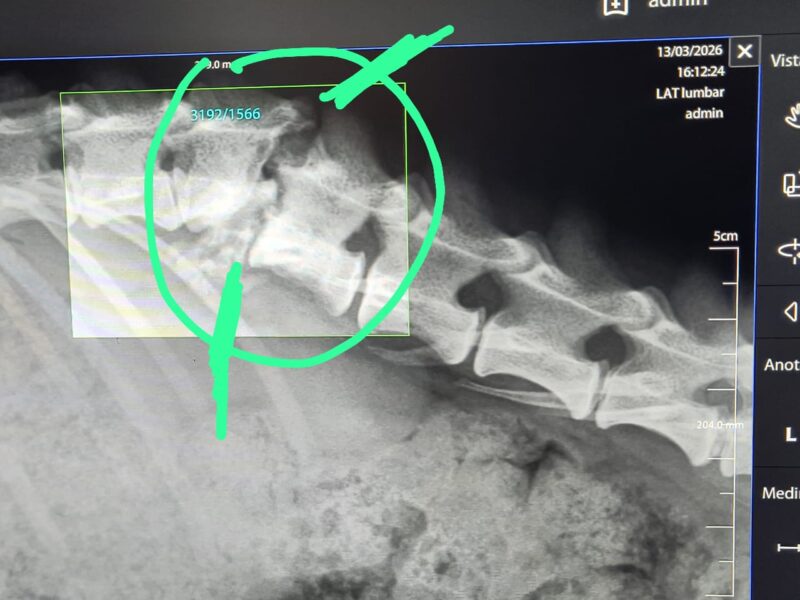

Actualmente está sano,sin embargo debido a que tiene fractura de médula arrastra de repente sus patitas traseras

Ya se llevó con varios especialistas ,los cuales coinciden en que NO es operable ,sin embargo el puede llevar una vida normal